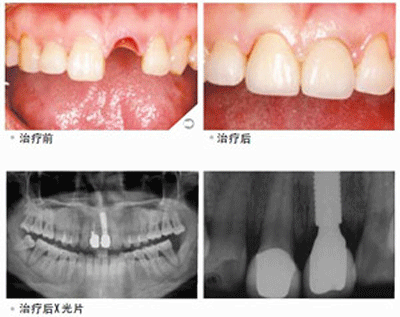

老人普遍缺牙,缺牙 好的修复方式就是做种植牙,但是很多人并不了解种植牙。那特别是对于老人来说,种植牙比活动义齿贵还麻烦有什么好的?那么老年人做种植牙到底好不好呢?

老年人牙齿缺失破坏了牙列的完整性,不仅影响口腔局部健康,更可蔓延至身体系统的病变。以前很多人还是选择活动义齿的方式来修复缺失牙,尽管或活动义齿的价格非常便宜,但是其舒适度、咀嚼力与美观性却差强人意。种植牙的出现就完美的克服了这些问题。但种植牙也不是说种就能种,有些疾病要控制好了才能考虑种牙,如患糖尿病、甲亢等疾病的人种牙前要控制好病情。若本身有较重牙周病者,则要治疗好后才可种植。

有很多人认为,老年人骨质相对疏松,牙槽骨吸收明显,做种植牙的效果可能不是那么好。事实上,相当一部分老年缺牙患者是适合做种植牙修复的。对于牙槽骨条件较差的患者,口腔医生可以在种植牙手术前植骨以增加牙槽骨的高度及宽度,术后牙槽骨完全可以满足种植牙的要求。